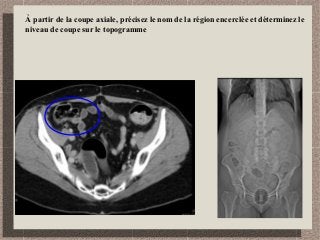

À partir de la coupe axiale, précisez le nom de la région encerclée et déterminez le

niveau de coupe sur le topogramme

Région iléo-cæcale